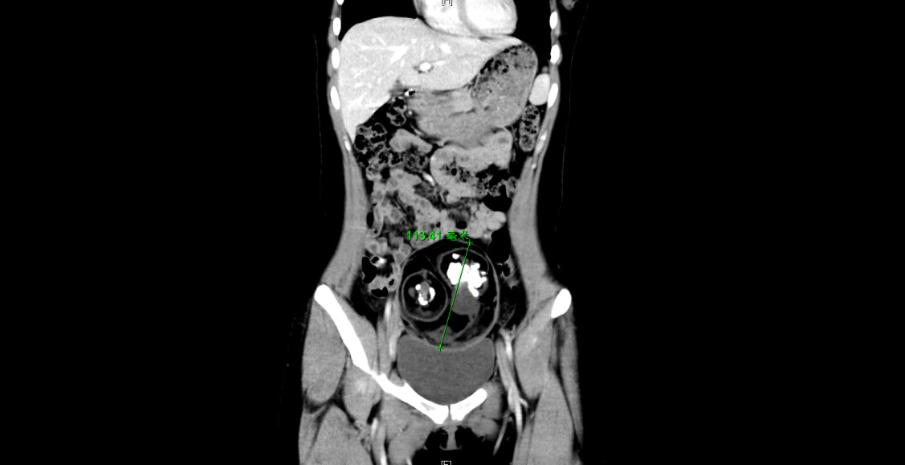

CT检查示下腹部有一直径约12厘米的肿块